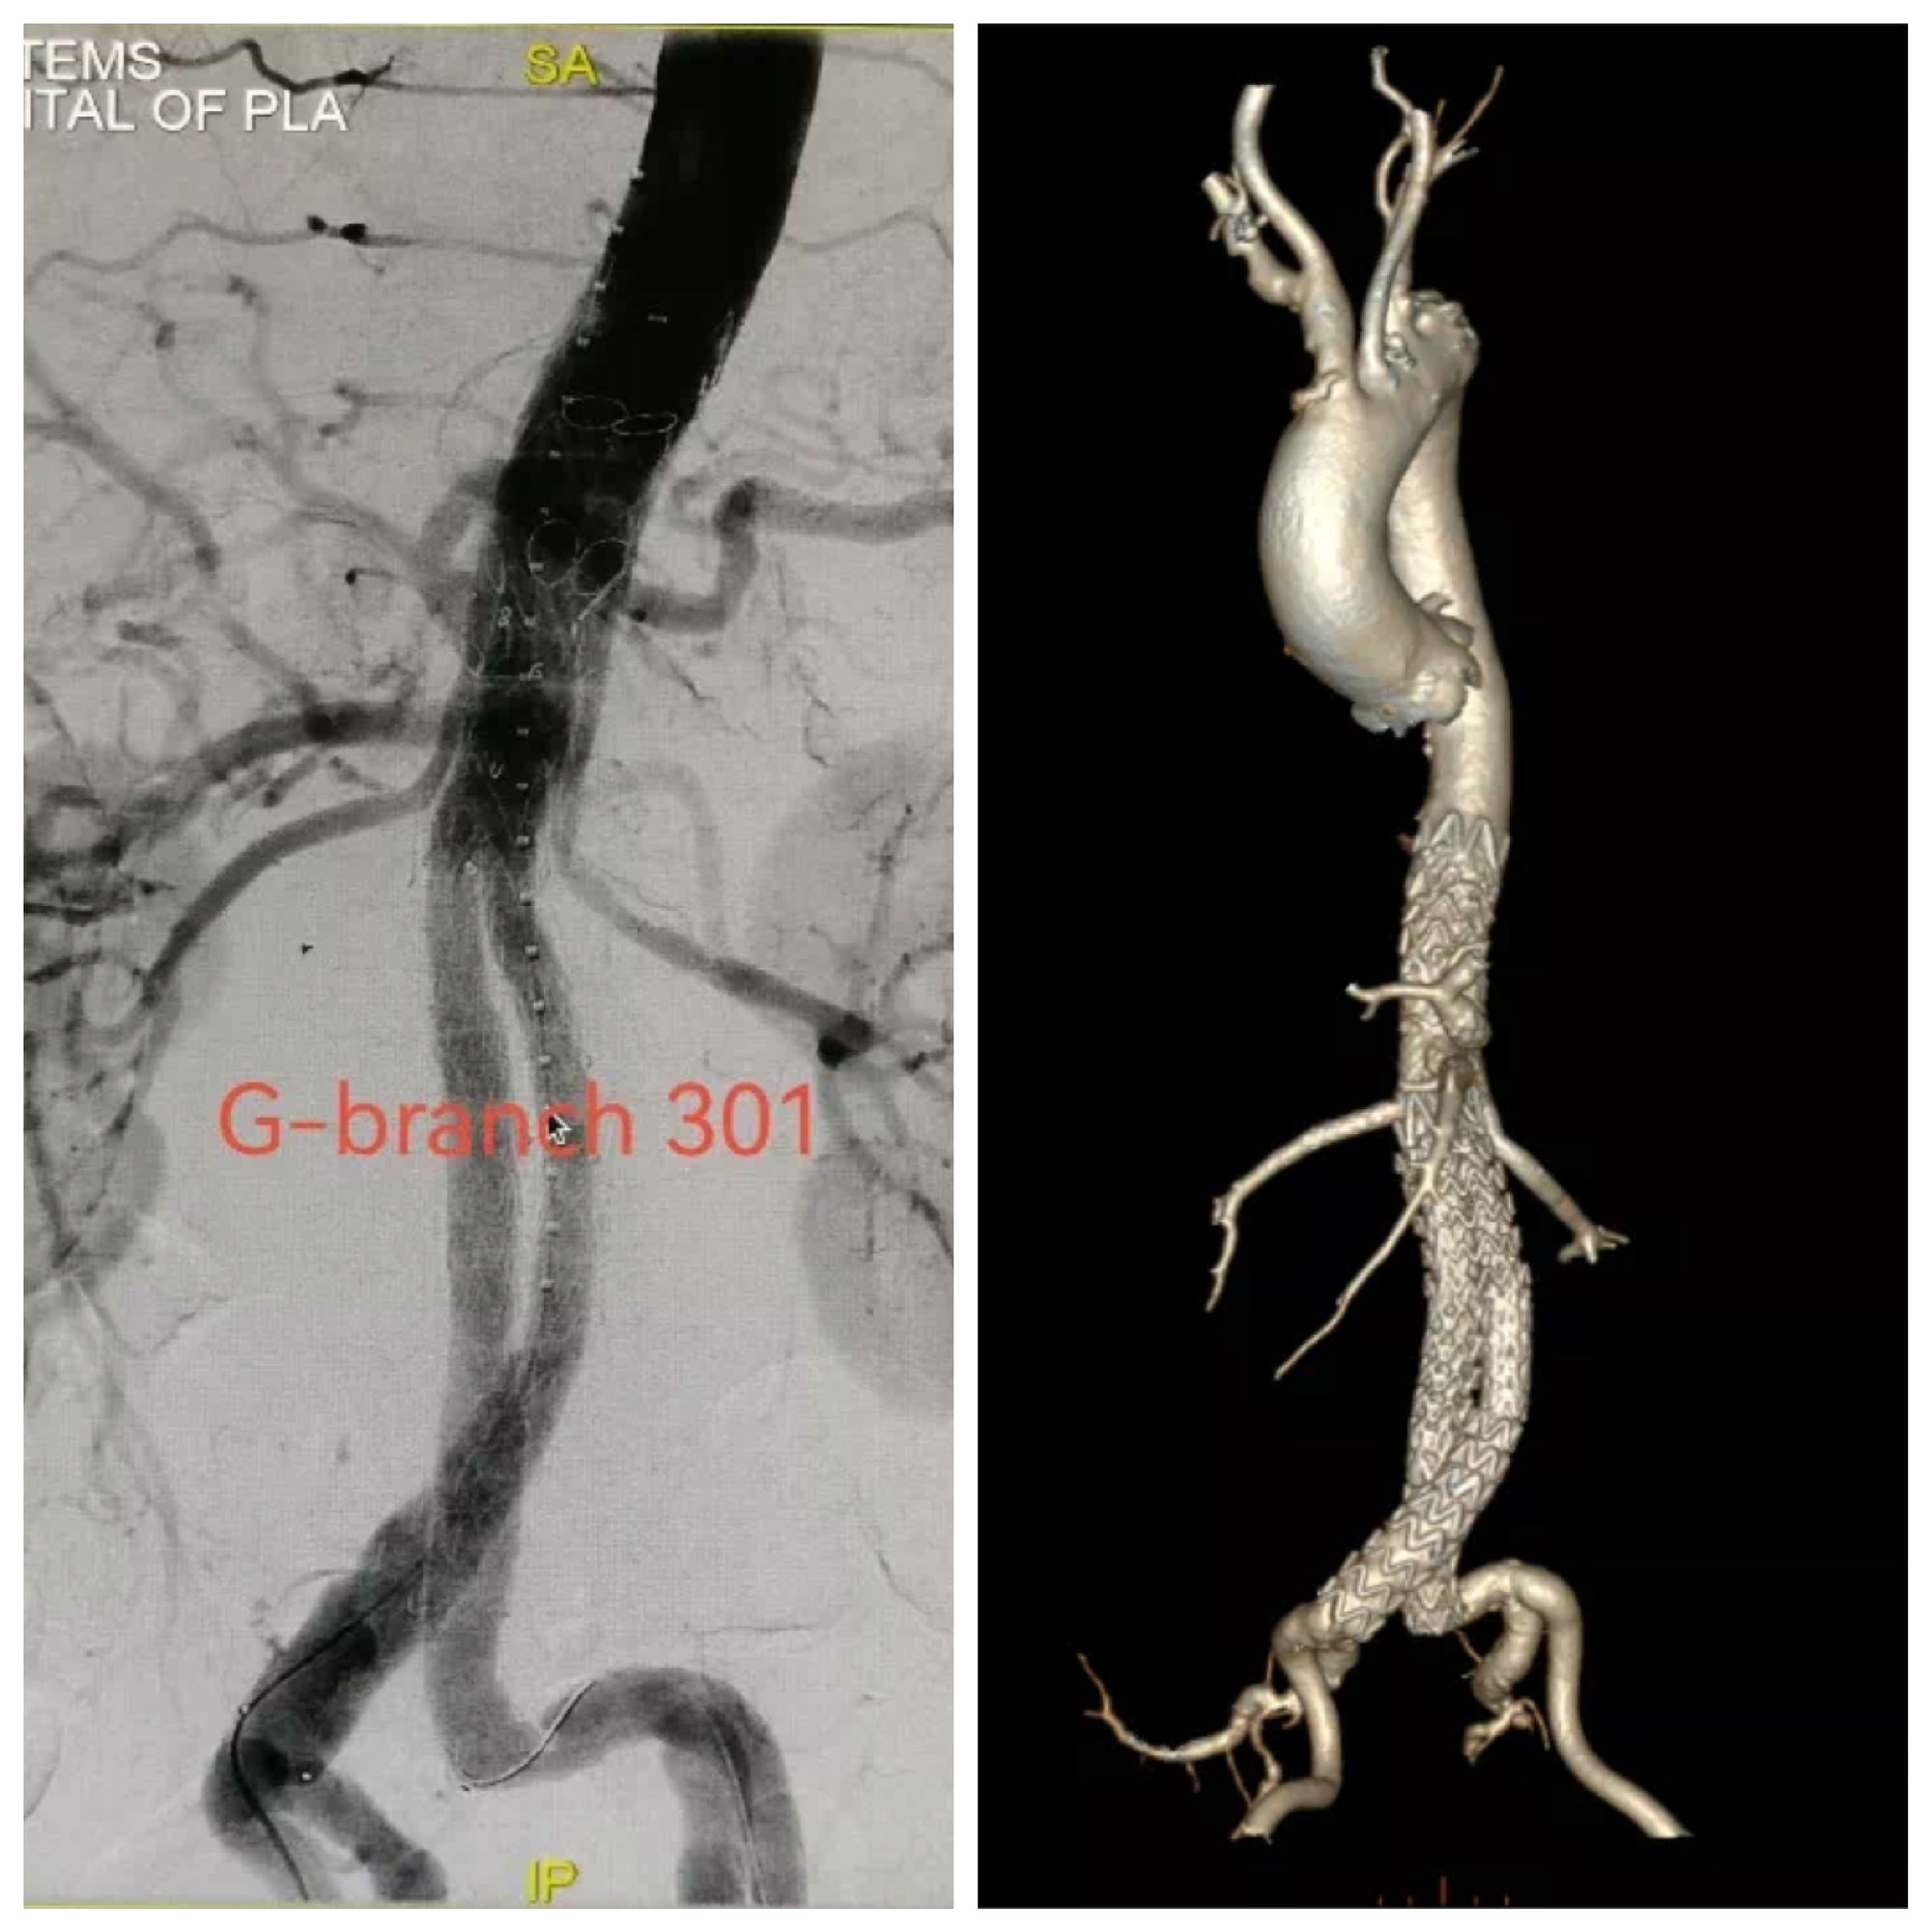

使用G-Branch™胸腹主动脉覆膜支架系统延长近端锚定区,腔内重建腹腔干、肠系膜上动脉及双肾动脉。

术后造影及出院前随访:

患者胸腹主动脉瘤隔绝完全,支架位置及形态良好,各分支动脉重建后血流通畅,无内漏发生。

术后,郭伟教授表示:“该患者为胸腹主动脉瘤先兆破裂急诊入院,既往EVAR术+肾动脉烟囱支架植入,肾动脉开口狭窄、病情危重,手术难度大。在急诊状况下应用G-Branch™及时重建了内脏动脉和肾动脉,让因I型内漏引起的濒临破裂的动脉瘤及时得到救治,这彰显了G-Branch非定制设计的优越性。混合内嵌分支设计理念的优越性在这例病变中得到了很好的呈现,在修复动脉瘤的同时最大化减少主动脉覆盖,从而有效降低截瘫并发症的发生风险。”